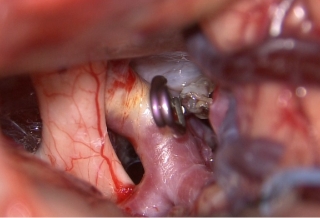

治療前

物が二重に見えるようになって発症した内頚動脈大型動脈瘤(矢印)の症例です。クリッピング術で直接動脈瘤をつぶすことができないため、バイパス術(矢印)を増設し内頚動脈を遮断することで動脈瘤を治療しました。